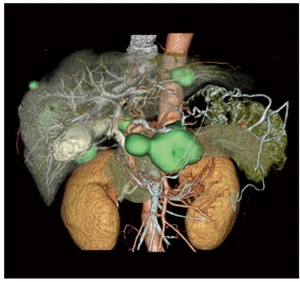

従来から定評のあるマルチモダリティフュージョンでは異なるフェーズ,異なるモダリティのデータを三次元的に重ね合わせることができる。例えば,腹部領域においては動脈と静脈を重ね合わせた画像で血管走行を把握できる。肝臓では動脈,静脈,門脈の3層を重ね合わせることができるため,術前シミュレーションに役立つ画像の提供が可能である。 (図4)また,CTとMRIそれぞれの特性を用いて評価する膵臓などの臓器において,CTとMRIのデータを重ね合わせることで双方の特長を生かした画像作成が可能である(図5)。これらは三次元的にリアルタイムで重ね合わせ位置を修正することが可能である。

図4 術前シミュレーションにも役立つ異なるフェーズを重ね合わせた画像

図5 CT,MRI,PETを重ね合わせた画像